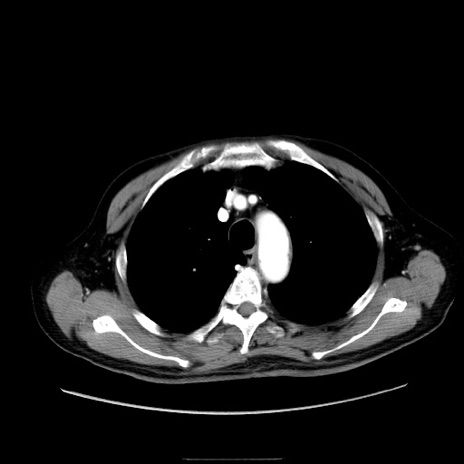

冠状断像